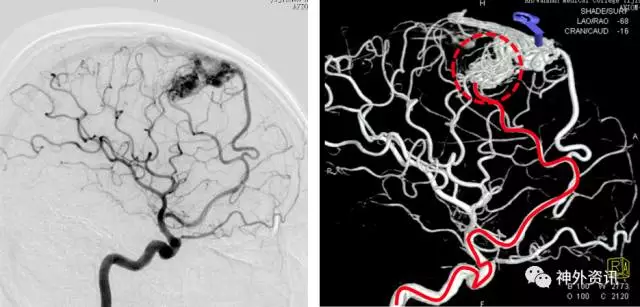

(DSA:烟雾病;左侧大脑后动脉P2段夹层动脉瘤)

(3D重建:动脉瘤形态极不规则,远/近端血管迂曲严重伴狭窄)

治疗难点:

1. 烟雾病患者,左侧椎动脉夹层动脉瘤,双侧大脑后动脉均承担前循环代偿供血任务,不能闭塞;故需行支架辅助弹簧圈栓塞治疗保护血管。

2. 椎动脉迂曲,病变血管迂曲严重伴狭窄,需要导引导管提供高稳定性和支撑力。 选择使用Envoy DA。